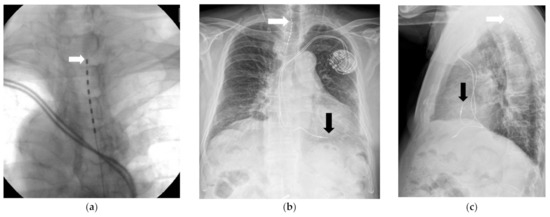

The SCS system (Implantable pulse generator (IPG): prodigy MRI, IPG, ST. JUDE Medical, Abbott, Chicago, IL, USA) trial was conducted in the operating room under monitored anesthesia management. While the patient was in a prone position, percutaneous local anesthesia was administered using 1% lidocaine using an aseptic technique. Using the loss-of-resistance method, a 16-gauge Tuohy needle was positioned between the T10 and T11 vertebrae, guided by a C-arm. The target area was confirmed by inserting a guidewire. Subsequently, the electrodes (percutaneous lead 8 pole, ST. JUDE Medical, Minneapolis, MN, USA) were positioned from T1/2 to T3/4 and directed toward the head (Figure 1a–c).

Figure 1.

(a) Spinal cord stimulation trial 180 days after the onset of rash. The arrow indicates the lead of the spinal cord stimulator. (b) A chest postero-anterior view, obtained on the next day, after the spinal cord stimulation trial. The white arrow indicates the lead of the spinal cord stimulator. The black arrow indicates the lead of the permanent cardiac pacemaker. (c) The chest lateral view obtained on the next day after the spinal cord stimulation trial. The shortest distance between the lead of the spinal cord stimulator and the lead of the cardiac pacemaker was 163.41 mm. The white arrow indicates the lead of the spinal cord stimulator. The black arrow indicates the lead of the permanent cardiac pacemaker.